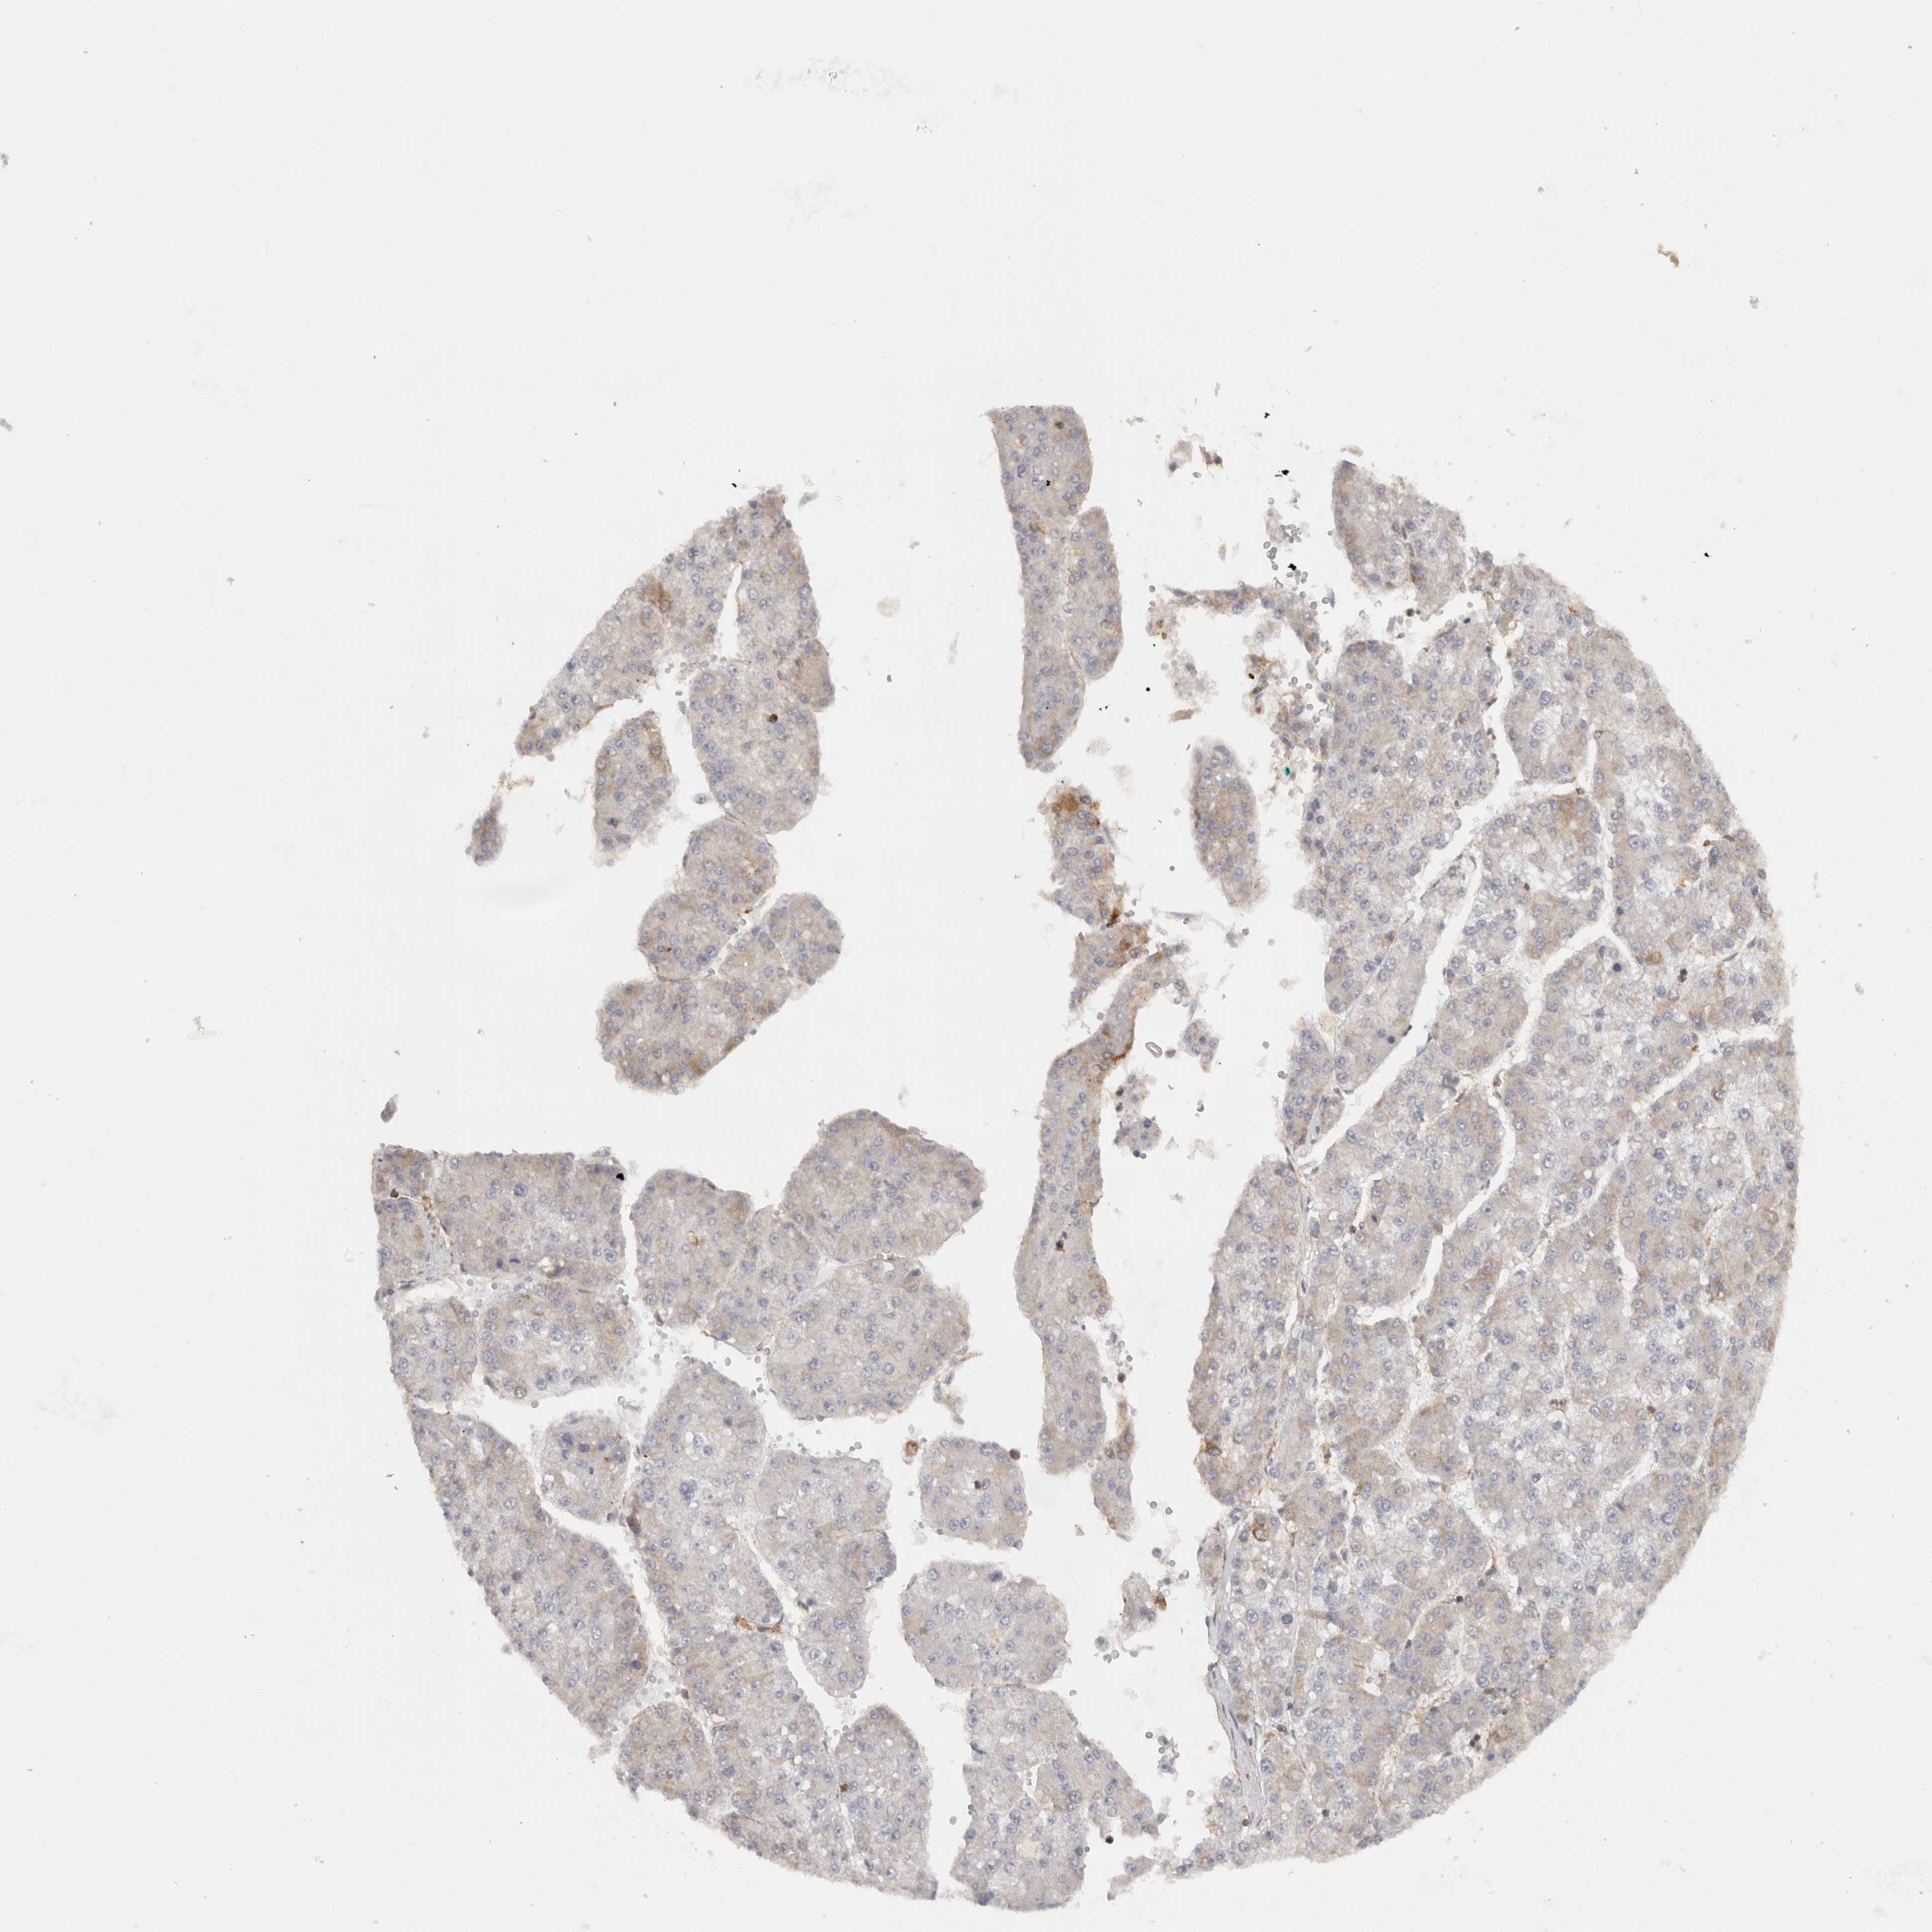

LIVER CANCER - Protein expressioni

A mouse-over function shows sample information and annotation data. Click on an image to view it in a full screen mode. Samples can be filtered based on level of antibody staining by selecting one or several of the following categories: high, medium, low and not detected. The assay and annotation is described here.

Note that samples used for immunohistochemistry by the Human Protein Atlas do not correspond to samples in the TCGA dataset.

Antibody stainingi

Antibody staining in the annotated cell types in the current human tissue is reported as not detected, low, medium, or high, based on conventional immunohistochemistry profiling in selected tissues. This score is based on the combination of the staining intensity and fraction of stained cells.

Each image is clickable and will lead to virtual microscopy that enables deeper exploration of all samples and also displays staining intensity scores, fraction scores and subcellular localization as well as patient and tissue information for each sample.

Antibody HPA031454

Antibody CAB024589

Cholangiocarcinoma

Carcinoma, Hepatocellular, NOS